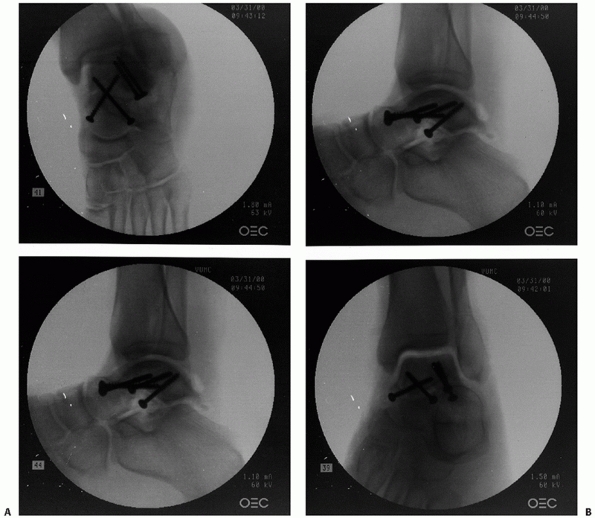

comminution and to confirm that varus malalignment has been avoided (Fig. 58-1).

FIGURE 58-2 Intraoperative fluoroscopic evaluation of the talus. A. A Canale and Kelly view and lateral image of the subtalar joint. B. Lateral and anteroposterior views of the ankle in a talar neck fracture with an associated lateral process fracture.